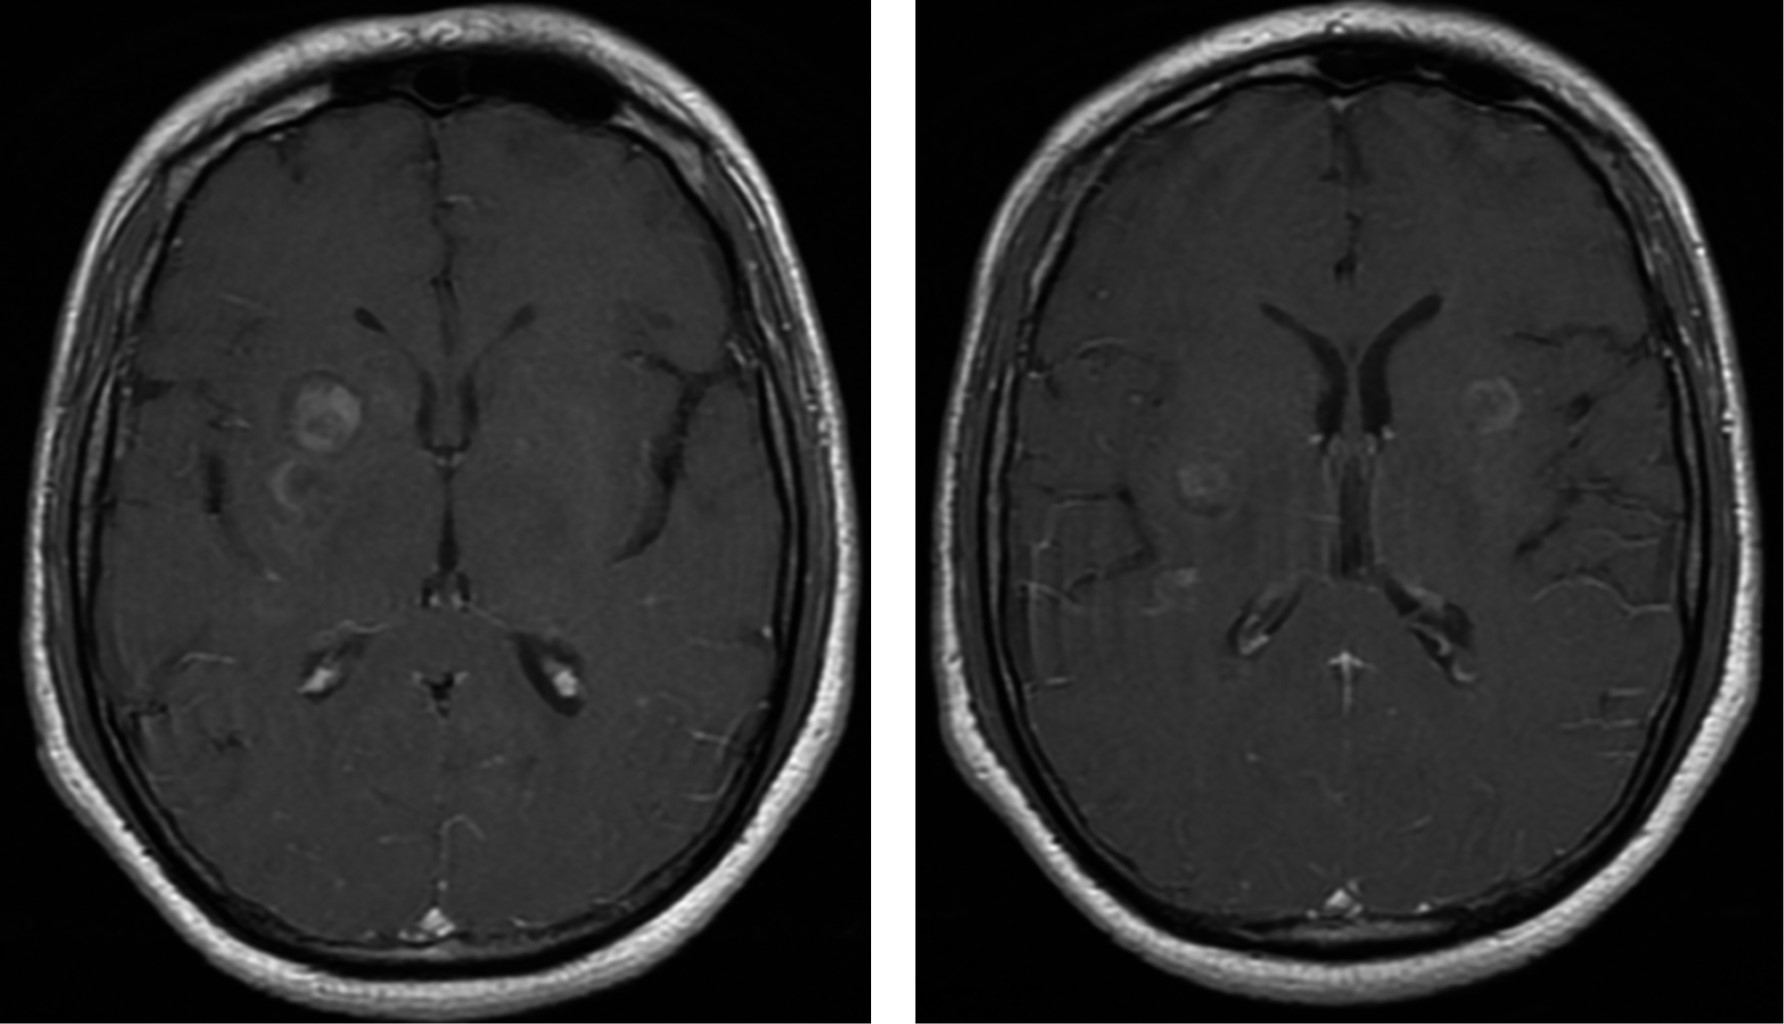

Se complementa estudio con resonancia magnética nuclear con contraste, la cual se muestra en la Figura 2. Y dados los hallazgos en probable relación con aumento de presión intracraneal, se realiza punción lumbar encontrando los siguientes resultados:

Figura 2